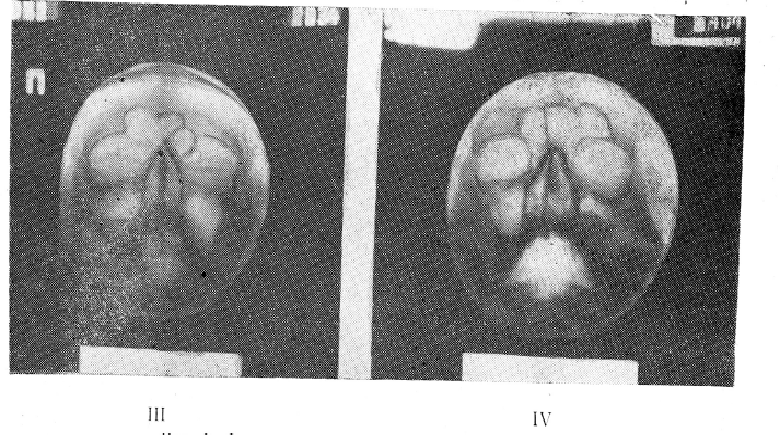

Из 76 больных с жидкостью в пазухах у 21 определялись горизонтальные уровни жидкости, у 14 — параболические границы, у 25 — сочетание жидкости и гиперплазии слизистой оболочки. Приводим несколько наших флюорографических наблюдений (рис. 1—I, II, III, IV).

Отображение патологических процессов в придаточных пазухах носа на флюорограммах имеет свои особенности. Так, пристеночные теневые наслоения в пазухах при острых катаральных и хронических гиперпластических процессах, а также полукруглые тени кист на флюорограммах представляются более интенсивными и подчеркнутыми, чем на рентгенограммах. В связи с исследованием больных в вертикальном положении, наличие жидкости в пазухах может давать на флюорограммах горизонтальные и параболические верхние контуры затенений. По той же причине кисты гайморовых полостей, уплощаясь, могут симулировать горизонтальные уровни жидкости, давая так называемый симптом уплощения кисты (А. И. Бухман). Однако при тщательном изучении флюорограмм в таких случаях удается заметить закругление «горизонтального уровня» книзу у наружной или медиальной стенок пазух. В сомнительных случаях правильно решить вопрос помогает рентгенография в горизонтальном положении больного. При этом киста приобретает обычные очертания с выпуклостью верхнего контура, а жидкость дает равномерное затенение пазухи.